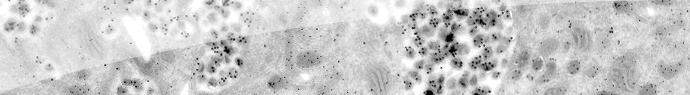

Un petit aperçu du VIH :

Schéma de la structure du VIH Merci au site Vie d'avoir accepté de partager cette image.

Tout d'abord, avant de nous attarder sur le VIH, faisons un petit rappel sur les virus en général. Un virus est inapte à la vie, il doit infester une cellule pour survivre, en détournant l'énergie qu'elle produit pour vivre et se reproduire. Ici, vous pouvez remarquer que le VIH ne possède pas d'ADN, mais de l'ARN (c'est une version transcrite de l'ADN). Des molécules, ici les RT polymérase, sont chargées d'effectuer cette transcription dans le sens inverse pour redonner de l'ADN une fois que le virus aura intégré la cellule hôte. Cette particularité fait du VIH un rétrovirus.